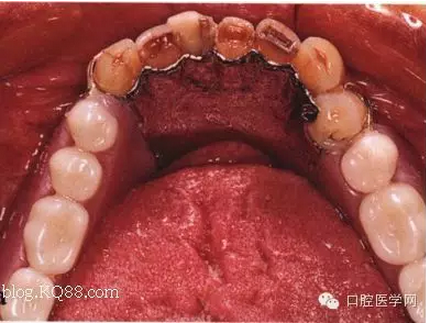

先注明一下:本文圖片部分來自李望松的支架設(shè)計(jì)圖譜收集u/210/archives/2008/25181.html,借圖表達(dá)一下,沒有別的目的,只是讓文章更生動些,李老師一直是我崇拜的偶像,只是近來很少見到他的文章,期待李老師的大作,言歸正傳——————修復(fù)大夫要精通支架設(shè)計(jì),作為一個修復(fù)大夫,是第一個獲得患者牙體狀況的,所以說在哪放個合支拖,在哪放個卡換,至關(guān)重要,因?yàn)槲覀冏龅氖莻€有創(chuàng)不可逆操作,既要兼顧牙周狀況,又要兼顧粘膜狀況,以及牙槽脊的情況,所以說當(dāng)給患者做完檢查以后我們頭腦中就應(yīng)該有一個大體支架了,以前,總是太依賴加工廠了,取完模剩下的好像都是交給了加工廠了,怎么設(shè)計(jì),你看摸著辦吧,仿佛設(shè)計(jì)那是加工廠的事,可是做了幾回再加上自己的學(xué)習(xí),經(jīng)驗(yàn),加工廠的設(shè)計(jì)總是不怎么樣,以前設(shè)計(jì)的方案仿佛根深蒂固,一直就認(rèn)為那是正確的就那么設(shè)計(jì),再加上以前看過支抗兄的一篇文章,也是深有感觸,一個不科學(xué)的設(shè)計(jì)方案,那樣就成了一個慢性拔牙器。看看幾幅圖片

看紅箭頭處為什么要空出一點(diǎn)距離?,看看自己加工廠設(shè)計(jì)的不管牙怎樣是不是都成了一個整體呢?對于愕板或者是

愕桿要離開齦緣4-6mm,以促進(jìn)食物對牙齦的按摩沖刷作用,促進(jìn)牙齦健康